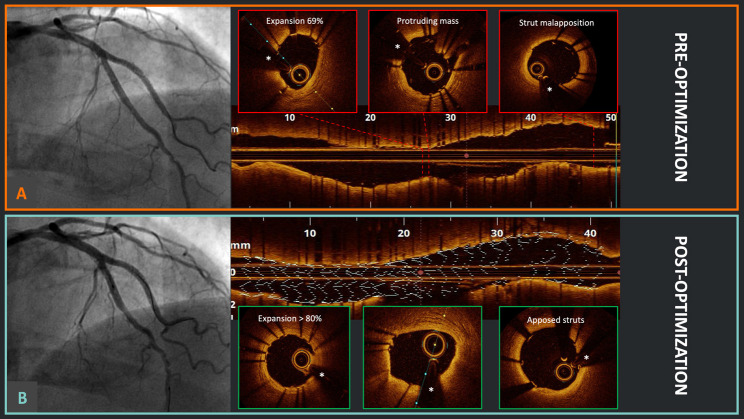

Abstract Image